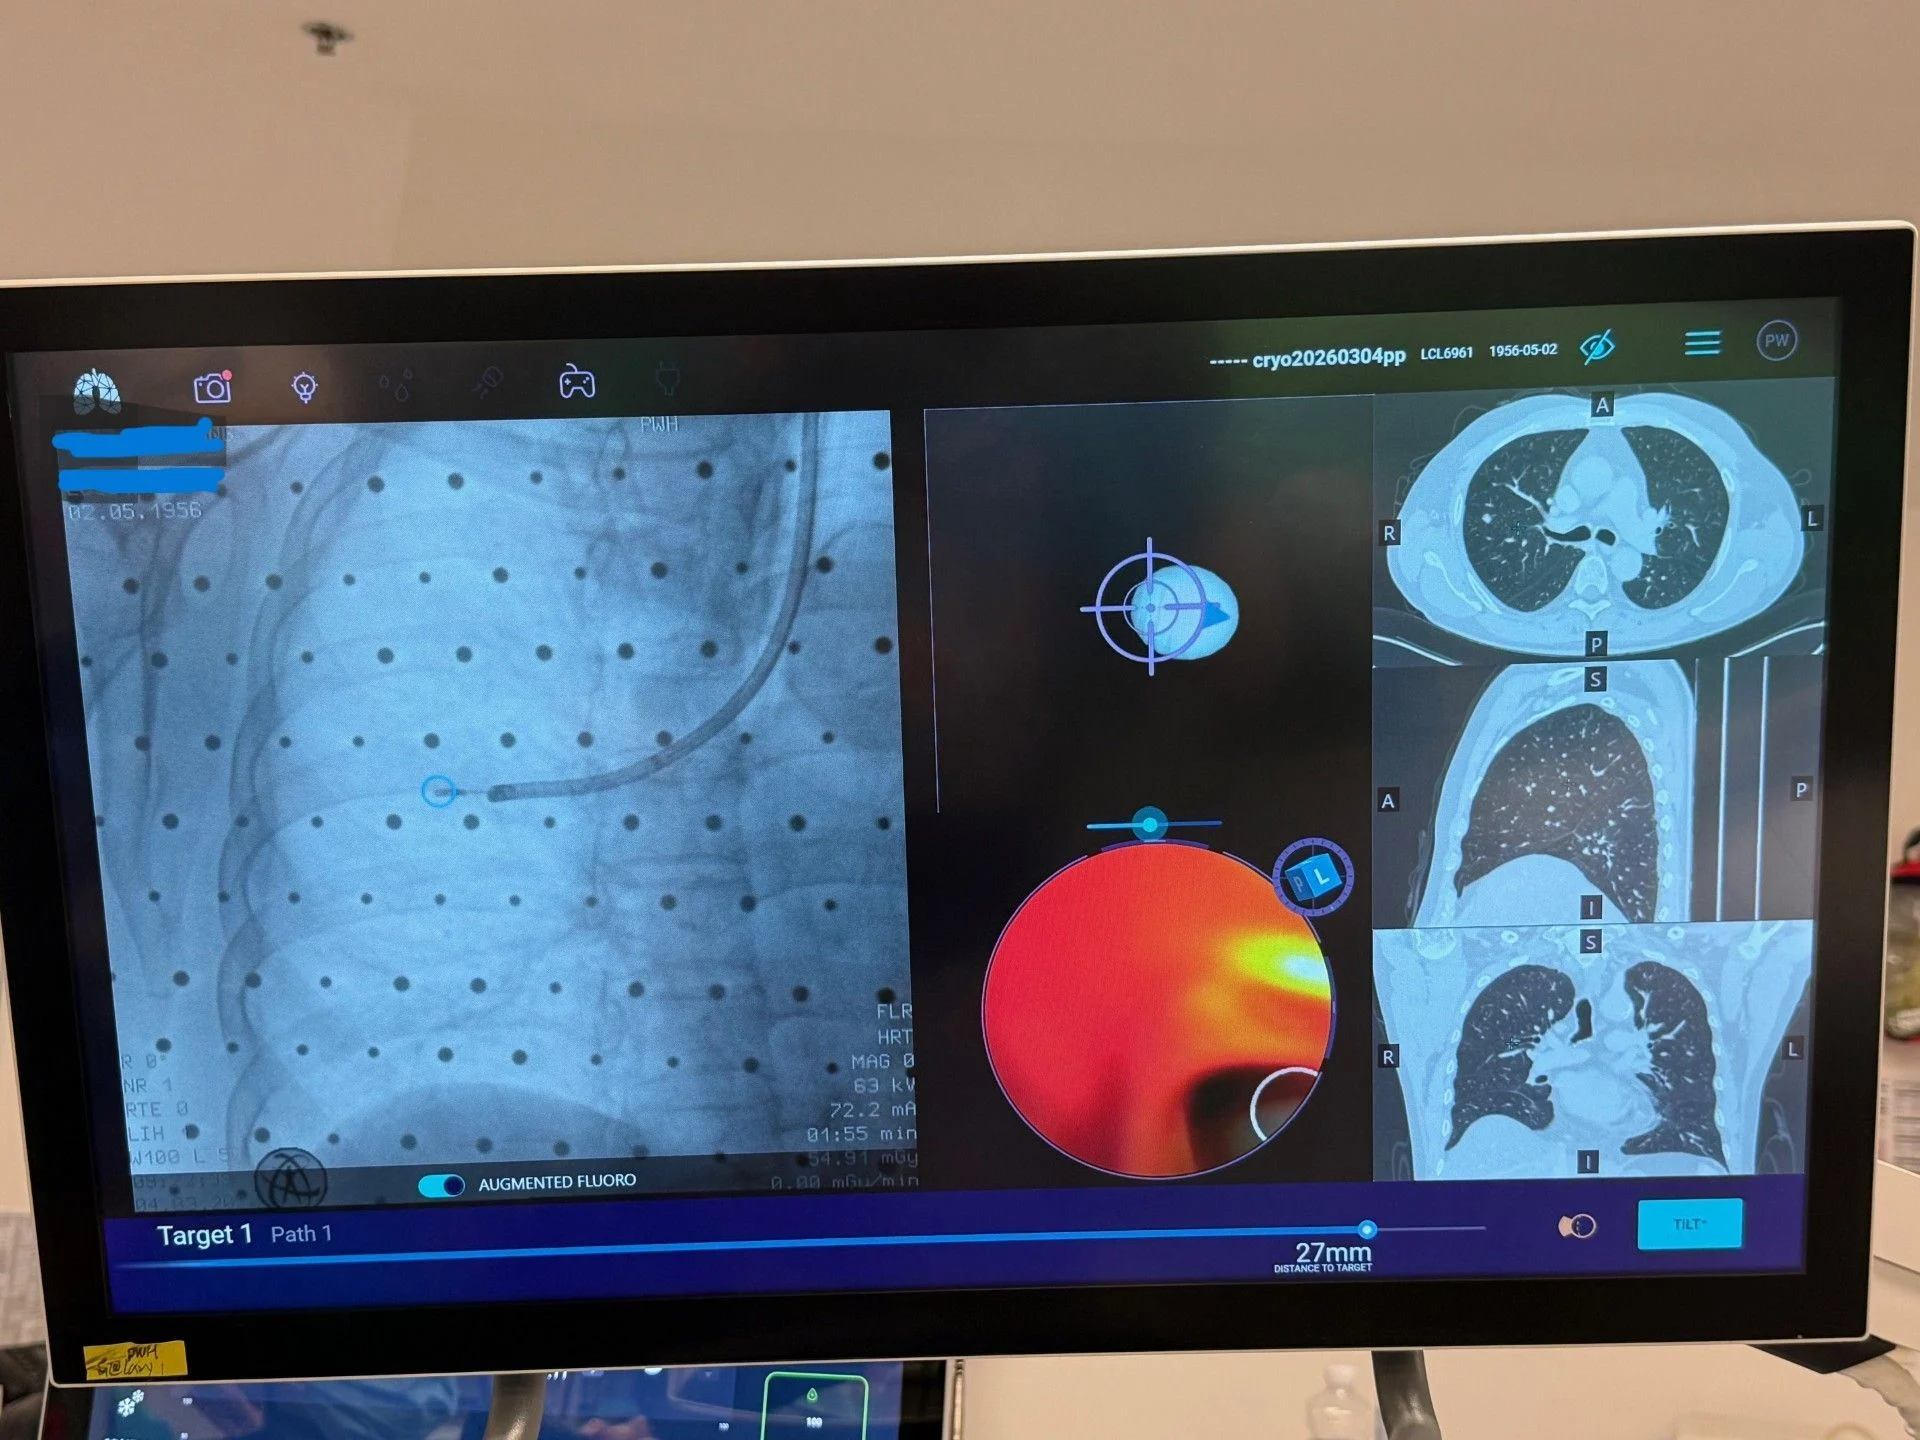

” Hong Kong’s First Cases (First outside Mainland China) Robotic Assisted Bronchoscopy Cryoablation for lung cancer and pulmonary metastases. Cryoablation (at -152 degrees Celsius) has its unique advantages over some other energy modalities, adding to our armamentarium of transbronchial microwave, RFA microperfusion, and PEF.